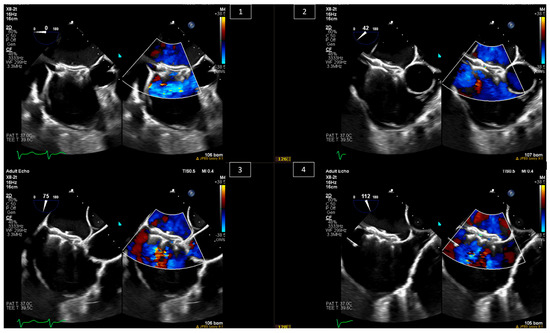

5. Paravalvular Leak Intervention